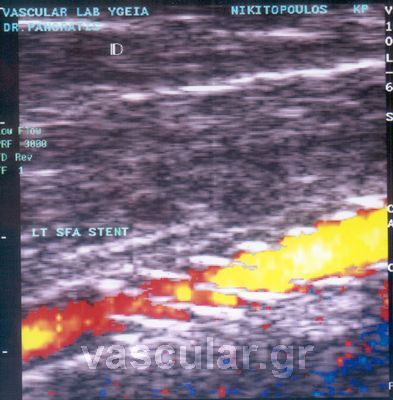

Duplex-Triplex åîÝôáóç

Ç Duplex-Triplex åîåôáóç åßíáé ç âáóéêÞ åîÝôáóç ãéá íá êáèïñéóèÞ ç âëáâç êáé áí ðñüêåéôáé ãéá óôÝíùóç Þ áðüöñáîç, êáèþò êáé ï ôýðïò ôçò áñôçñéïóêëÞñõíôéêÞò áëëïéþóåùò, ï âáèìüò ôçò óôåíþóåùò êáé ôçò õöÞò áèçñùìáôéêÞò ðëÜêáò, åßíáé åîåôÜóåéò áíáßìáêôåò, áíþäõíåò, ÷ùñßò íá ãßíåé åðéâÜñõíóç ãéá ôïí ïñãáíéóìü êáé åýêïëá åðáíáëáìâáíïìÝíç . Ïé åîåôÜóåéò áõôÝò ðñÝðåé íá ãßíïíôáé áðü åîåéäéêåõìÝíï éáôñéêü êáé åðéóôçìïíéêü ðñïóùðéêü.

ÃåíéêÜ ðïý åõñßóêåôáé êáé ðüóï óïâáñÞ åßíáé ç íüóïò ìðïñåß íá åîáêñéâùèåß áðü áõôÞ ôçí åîÝôáóç. Ôï Õðåñç÷çôéêü Doppler êáé ç triplex åîÝôáóç äåí ÷ñçóéìïðïéåß åíÝóåéò , óêéáãñáöéêü, áêôéíïâïëßá êáé åßíáé ôåëåßùò áíþäõíï êáé áêßíäõíï

EíäïáõëéêÝò ðñïèÝóåéò ( stents)

Ç åíäïáõëéêÞ ðñüèåóç åßíáé ðñïóöÜôïõ åðéíïÞóåùò êáé ó÷åäéáóìïý ãéá íá êñáôÜíå ôïí áõëü ôïõ áããåßïõ áíïéêôü ðïõ ðñïçãïõìÝíùò äçìéïõñãÞèçêå áðüöñáîç Þ óôÝíùóç. Áêïëïõèåß ôçí áããåéïðëáóôéêÞ ìå ìðáëüíé, ïé áñôçñßåò ìåñéêÝò öïñÝò ìåôÜ áðü êÜèå áããåéïðëáóôéêÞ îáíáóôåíåýïõí ìå áðïôÝëåóìá íá Ý÷ïõìå ôá ßäéá óõìðôþìáôá üðùò ðñéí ôçí åðÝìâáóç. Ó áõôÞ ôçí ðåñßðôùóç îáíáãßíåôáé ç áããåéïðëáóôéêÞ ìå ìðáëüíé êáé ôïðïèåôåßôáé ç åíäïáõëéêÞ ðñüèåóç Þ åÜí äåí åßíáé äõíáôüí ãßíåôáé ðëÝïí ç êëáóéêÞ áããåéï÷åéñïõñãéêÞ åðÝìâáóç ìå BY-Pass äçë. ÷åéñïõñãéêÞ áðïêáôÜóôáóç êáé ðáñÜêáìøç ôçò âëÜâçò.

Ôá stents Þ åíäïáõëéêÝò ðñïèÝóåéò ôïðïèåôïýíôáé ìïíßìùò äçë. äåí áöáéñïýíôáé ìåôÜ , ôïðïèåôïýíôáé óôéò óôåöáíéáßåò áñôçñßåò óôá ðåñéöåñéêÜ áããåßá äçë. íåöñéêÝò, ëáãüíéåò , ìçñéáßåò, éãíõáêÝò , õðïêëåßäéåò , âñá÷éüíéåò êëð. êáèþò åðßóçò êáé óôá öëåâéêÜ ìïó÷åýìáôá BY-Pass .

ÅíäáããåéáêÞ ôïðïèÝôçóç åíäáõëéêþí íáñèÞêùí ( stents

Ïé Åíäáõëéêïß ÍÜñèçêåò (ÅÍ) åßíáé óõóêåõÝò ðïõ, åéóáãüìåíåò óõíÞèùò äéáäåñìéêþò åíôüò ôïõ áããåéáêïý áõëïý, äýíáíôáé íá äéáôáèïýí ãéá íá åíéó÷ýóïõí ôï ôïß÷ùìá ôïõ áããåßïõ

Åßíáé Ýíá ìåôáëëéêü äéêôõùôü ðëÝãìá óå ó÷Þìá êõëßíäñïõ ôïðïèåôçìÝíï óå êáôÜëëçëï êáèåôÞñá ìðáëüíé êáé áöïý ôïðïèåôçèåß óôï óçìåßï ðïõ èÝëïõìå, íá äéáíïßîåé óôçí áñôçñßá, ôï ìðáëüíé öïõóêþíåé êáé åäþ ç åíäïáõëéêÞ ðñüèåóç stent áíïßãåé êáé åðéêïëëÜôáé óôá ôïé÷þìáôá ôïõ áããåßïõ êñáôüíôáò ôï áíïéêôü. Ï êáèåôÞñáò ìåôÜ áöáéñåßôáé êáé ôï áßìá ðëÝïí ðåñíÜ ÷ùñßò êáíÝíá åìðüäéï . Ôï stent Þ (åíäïáõëéêÞ ðñüèåóç) ìÝíåé ìüíéìá óôçí áñôçñßá åìðïäßæïíôáò ôçí íá îáíáêëåßóåé.